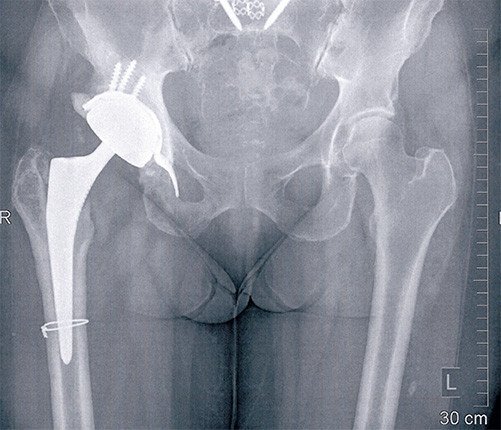

Diese Situation wurde dann für 8 Wochen so belassen. Während dieser Zeit erhielt die Patientin für 6 Wochen eine antibiotische Behandlung. Nach 8 Wochen wurde die Hüfte erneut eingesetzt. Verwendet wurde wieder ein zementfreier Schaft und pfannenseitig eine Stützschale, die eine luxationssichere Pfanne aufnimmt. Die Patientin ist infektfrei und mit dem Verlauf nun zufrieden.